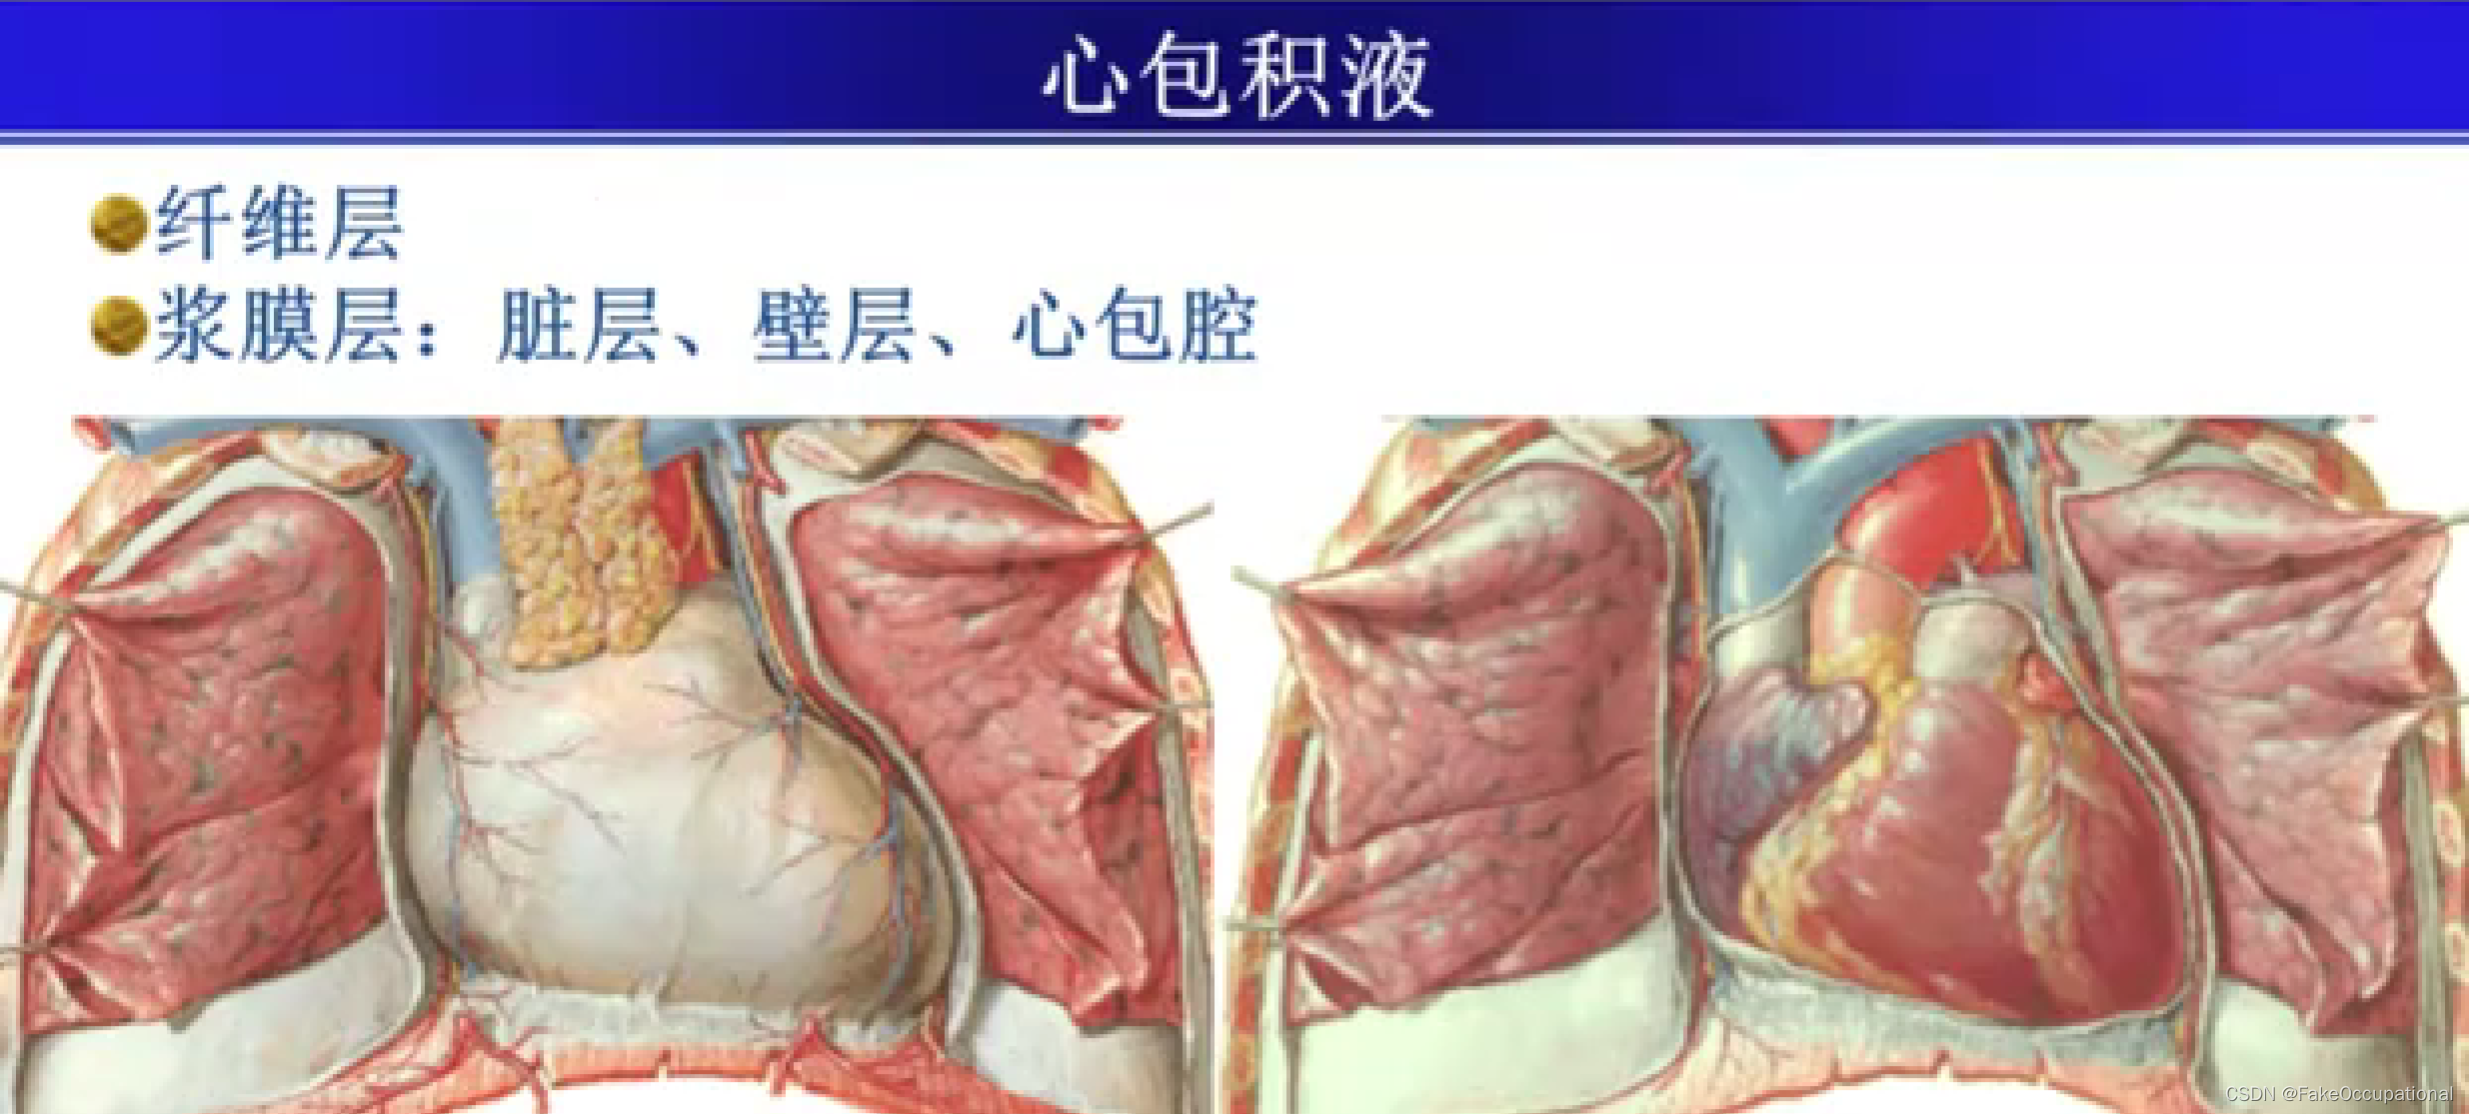

心包积液及心脏肿瘤

- 心包积液可出现于整个心包,也可局限于心包的局部,但心底部上方和心房后方很少发生液体积聚。心包积液时,心包腔可向内、外侧及心尖方向扩大。心包积液是心包炎最重要的表现之一,但心包炎并非必然出现心包积液。

心包积液超声定量

- 微量 (<50ml) : 左室后壁D2-3mm,右室前壁无液暗区;少量 (50-200ml) :左室后壁D10mm以内,右室前壁无或可疑液暗区;

- 中量 (200-500ml) : 左室后壁D10-20mm,右室前壁D5-10mm;

- 大量 (>500ml) :左室后壁D>20mm,右室前壁D>15mm,可出现心脏摆动征